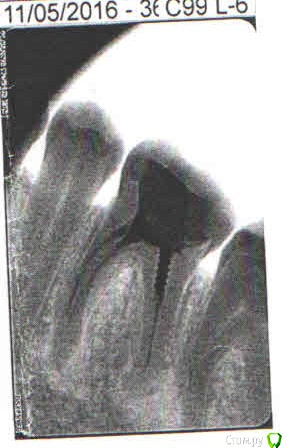

nashe72 Опубликовано 15 сентября, 2018 Поделиться Опубликовано 15 сентября, 2018 (изменено) Здравствуйте.Можно ли спасти этот зуб или только удаление? Боли нет, но постоянно чувствую дискомфорт в его области, пульсацию, "токанье". Также чувствую постоянный запах, думаю от него, так как другие зубы здоровы. Боюсь негативных последствий и очень жалко основной жевательный зуб. [ Изменено 15 сентября, 2018 пользователем nashe72 Ссылка на комментарий